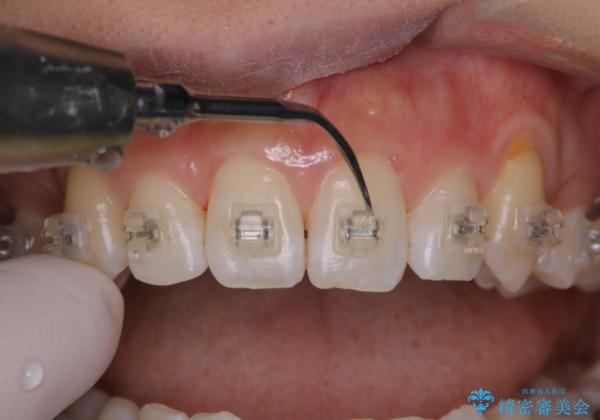

ワイヤー矯正中のPMTC

- ワイヤー矯正中に装置の周りの着色が気になるとのことで来院されました。PMTC30分コースを行いました。

ワイヤー矯正中も、歯の表面に着色(ステイン)が付着することがあります。着色(ステイン)が付着したままだと審美的な問題以外にも、虫歯を発見しずらいことや、細菌が繫殖しやすくなることがあります。クリーニングを行うことで、虫歯や歯周病予防に効果的だったり、もちろん見た目も審美的です。クリーニング後には、汚れが取り除かれ、お口の中がスッキリ・爽快感で気持ちがよくなります。矯正中も定期的にPMTCを行うことが大切です。